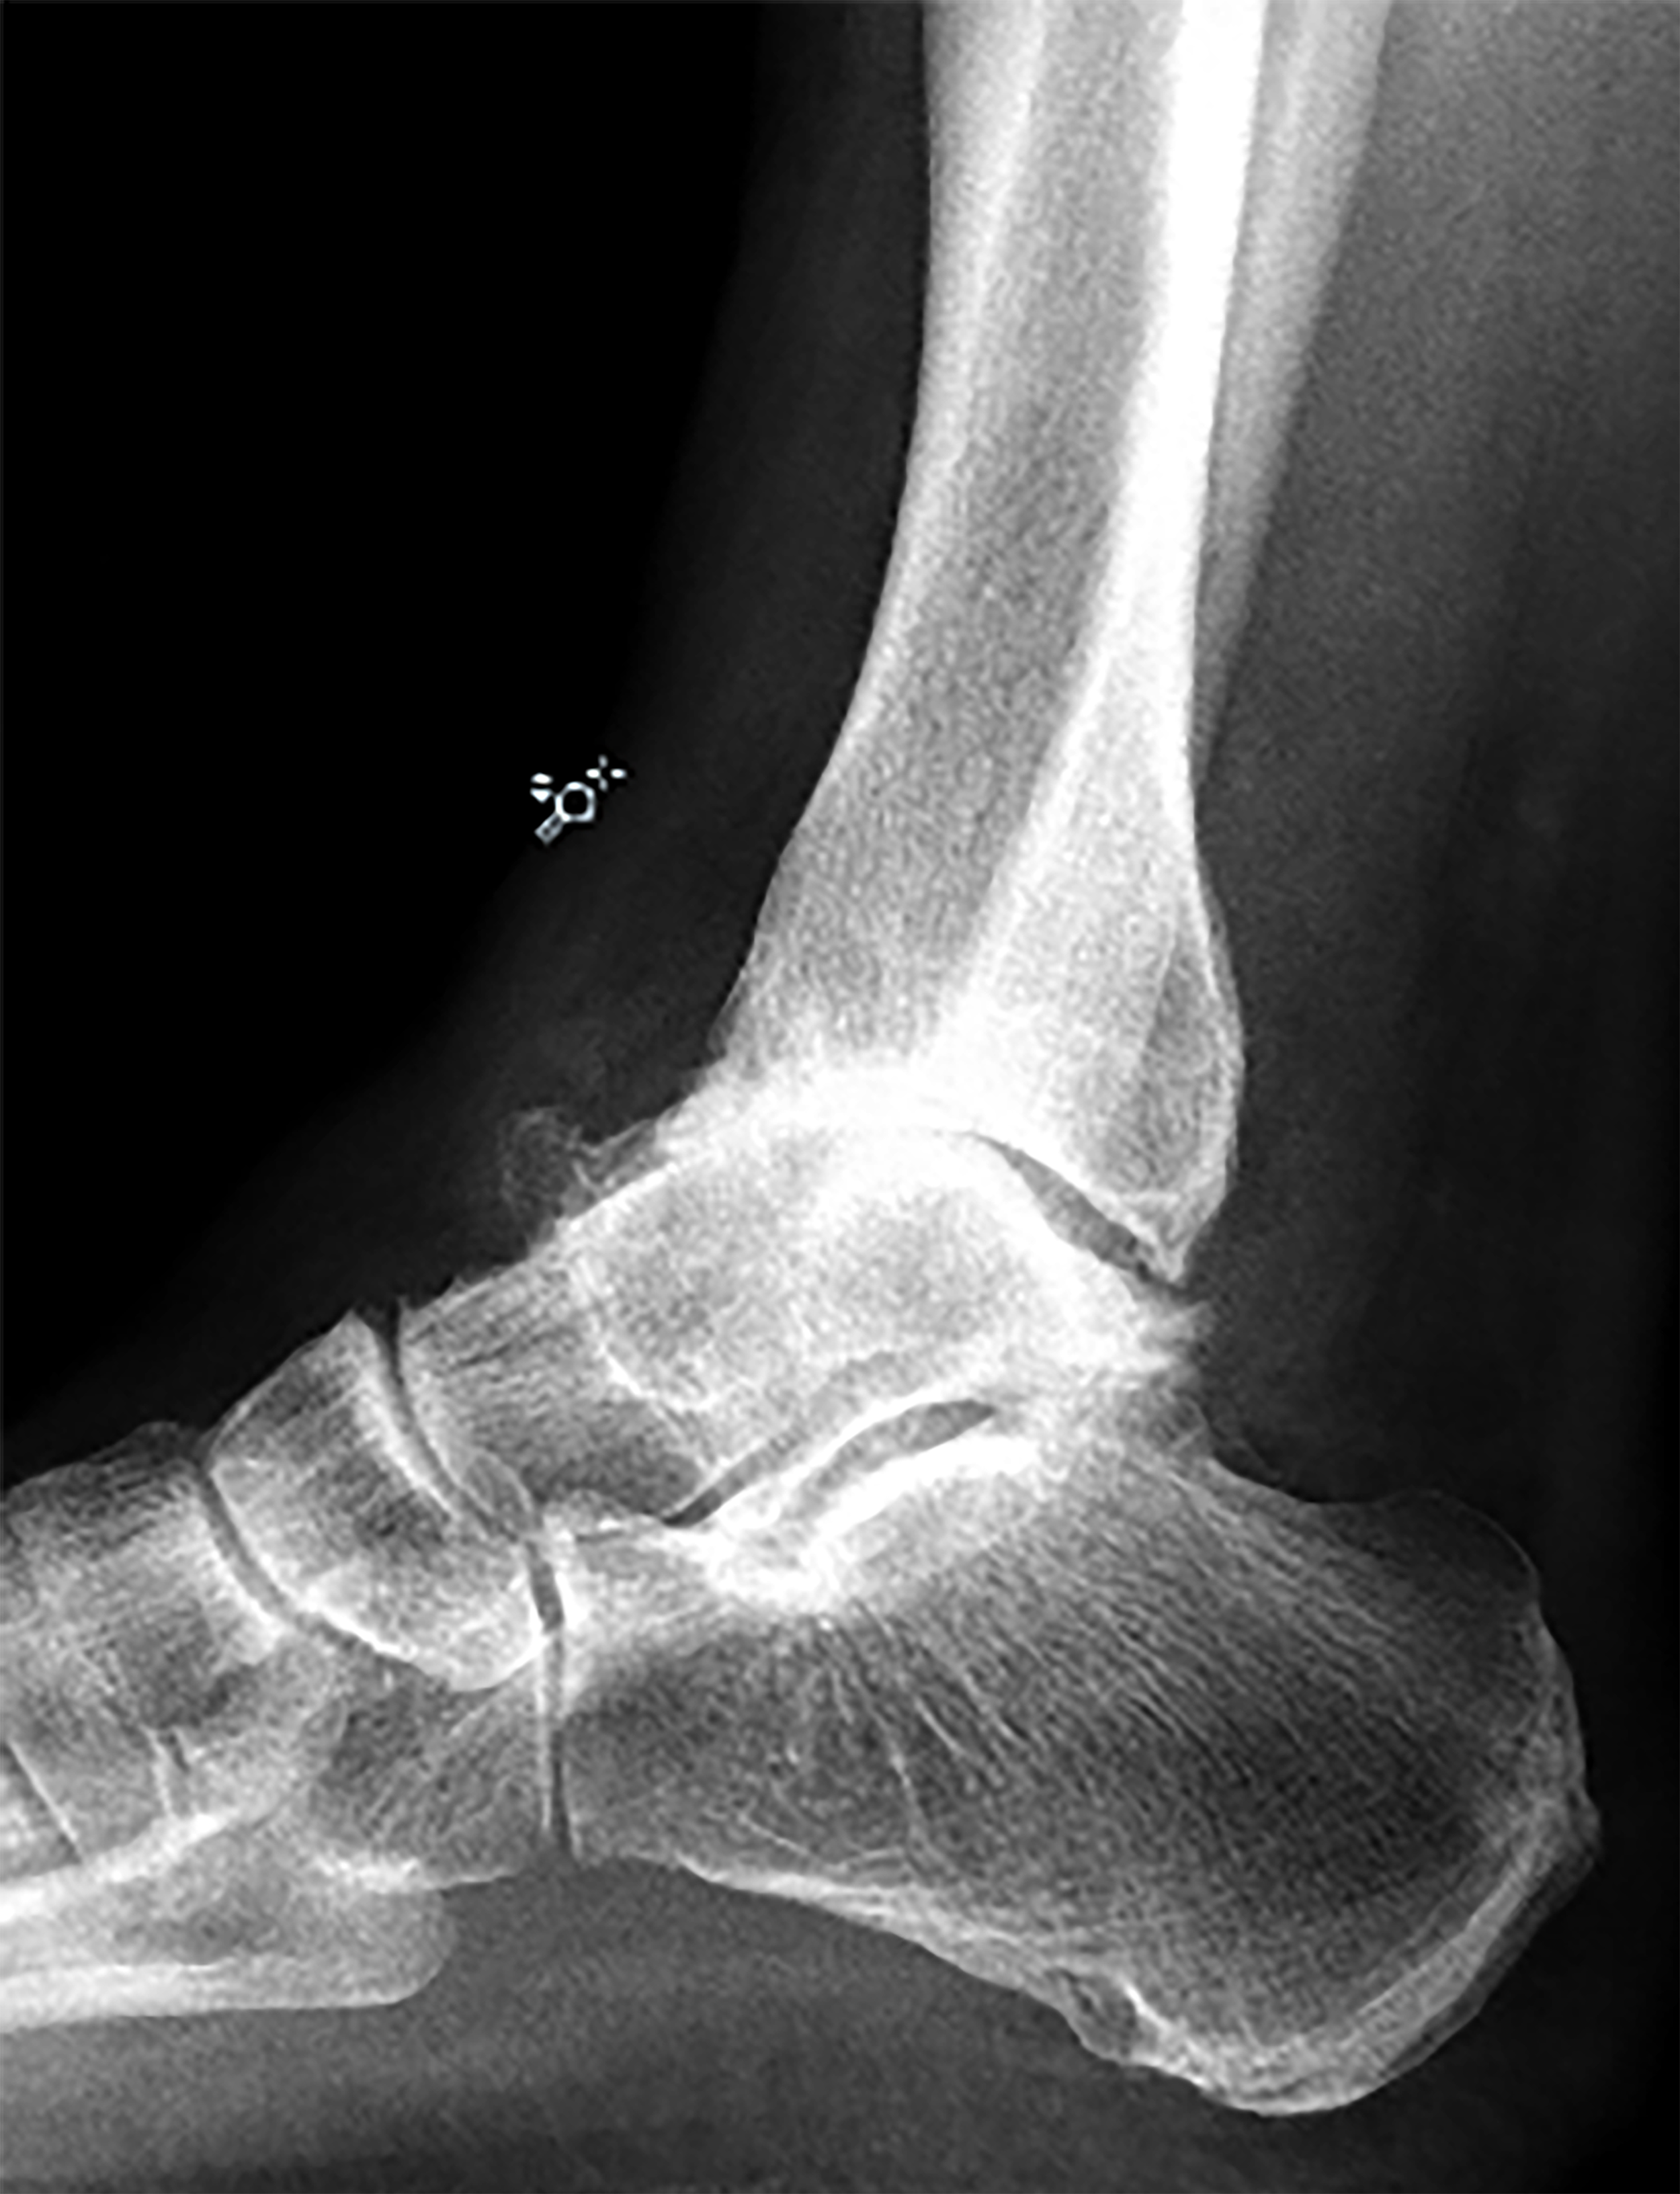

Bij het bovenste spronggewricht ontstaan er vaak botuitsteeksels (= osteofyten). Met name aan de voorzijde van de enkel ontstaan osteofyten, waardoor een beklemming kan ontstaan bij het omhoog bewegen van de enkel: de enkel stagneert. Ook kan er een klein stukje van de uitsteeksels afbreken, dit stukje kan gaan zweven in de enkel en kan ook een blokkade van de enkel geven.

De slijtage van de enkel kan zowel aan de voor- als achterzijde van de enkel zitten. Vaak staat de enkel een beetje uit het lood, waardoor bijvoorbeeld de binnenzijde van de enkel meer belast wordt in vergelijking met de buitenzijde. De slijtage in de enkel is dan ook vaak ook niet overal even erg.

Op de foto's is duidelijke slijtage/artrose aanwezig van het bovenste spronggewricht